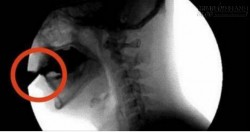

Thật sự, dù loại nước mát lạnh này có thể thỏa mãn nhiều người, nhưng bạn có biết mình đang uống những gì, ngoài khí ga tạo bọt trong nước - thứ làm tăng tiết dịch vị, tăng nồng độ axit trong dịch dạ dày và sinh nhiều khí thừa trong đường ruột...